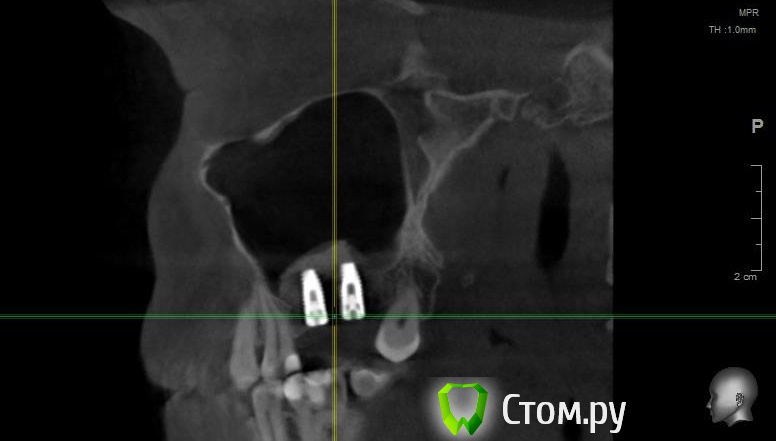

Майло Опубликовано 17 февраля, 2014 Автор Поделиться Опубликовано 17 февраля, 2014 (изменено) Попыталась загрузить снимок кт который был сделан до операции и еще один на всякий случай отснятый на телефон. Изменено 17 февраля, 2014 пользователем Майло Ссылка на комментарий

Майло Опубликовано 18 марта, 2014 Автор Поделиться Опубликовано 18 марта, 2014 (изменено) Здравствуйте, наконец сделала кт. Сегодня появилась небольшая боль над правой бровью (после лазера прошла, к вечеру появилась опять). Насморк и заложенность присутствуют. Еще сегодня опять поговорила со своим хирургом имплантологом. По симптомам сказал, что похоже присоединилась какая-то лор болячка и наверное надо сходить к лору. По кт сказал, что все нормально. Немного сужена пазуха справа, но учитывая, что я аллергичная, это нормально. Про капли типа Полидекса, сказал спросить у лора. Завтра я делаю последний лазер, по прежнему промываю нос Отривином Бэби (мне так удобней), пью кларитин, "выбиваю" нос по необходимости, но стараюсь пореже (2-3 раза в день). Еще он отдал кт через 2 недели после имплантации, на всякий случай прикреплю и этот снимок. Самый первый снимок кт был сделан через 2 недели после имплантации. Второй и третий сегодня. Подскажите, я так понимаю данное кт не показывает есть ли у меня гайморит? (к лору смогла записаться аж на 26-е) И все равно хотелось бы узнать ваше мнение по поводу состояния имплантов, есть ли там воспаление или "нагноение"? Изменено 18 марта, 2014 пользователем Майло Ссылка на комментарий

Майло Опубликовано 18 марта, 2014 Автор Поделиться Опубликовано 18 марта, 2014 (изменено) Решила еще добавить пару кадров своих пазух, вначале показалось что справа что-то есть (рис1), потом поняла это костный материал и импланты (рис2). Надеюсь так должно быть. И еще вопрос, может и "тупой", такое яркое свечение имплантов, особенно заметно на фото в профиль, это нормально? Изменено 18 марта, 2014 пользователем Майло Ссылка на комментарий